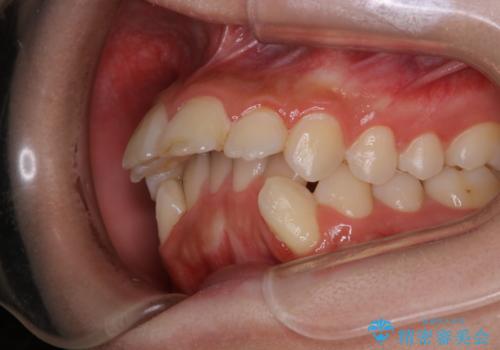

出っ歯と深い噛み合わせ:抜歯矯正で口元スッキリ!

- 出っ歯が気になるとご相談にいらした方です。抜歯して歯を並べました。深かった噛み合わせも改善させることが出来ました。

噛み合わせが元々深い方は一般的に噛む力が強く、治療に時間がかかる傾向にあります。治療前の想定よりも短期間でスムーズに治療を終える事ができ、大変喜んでいただけました。リテーナーによる保定もしっかり行っていただいており、後戻りなく快適にすごして頂けているとのことです。